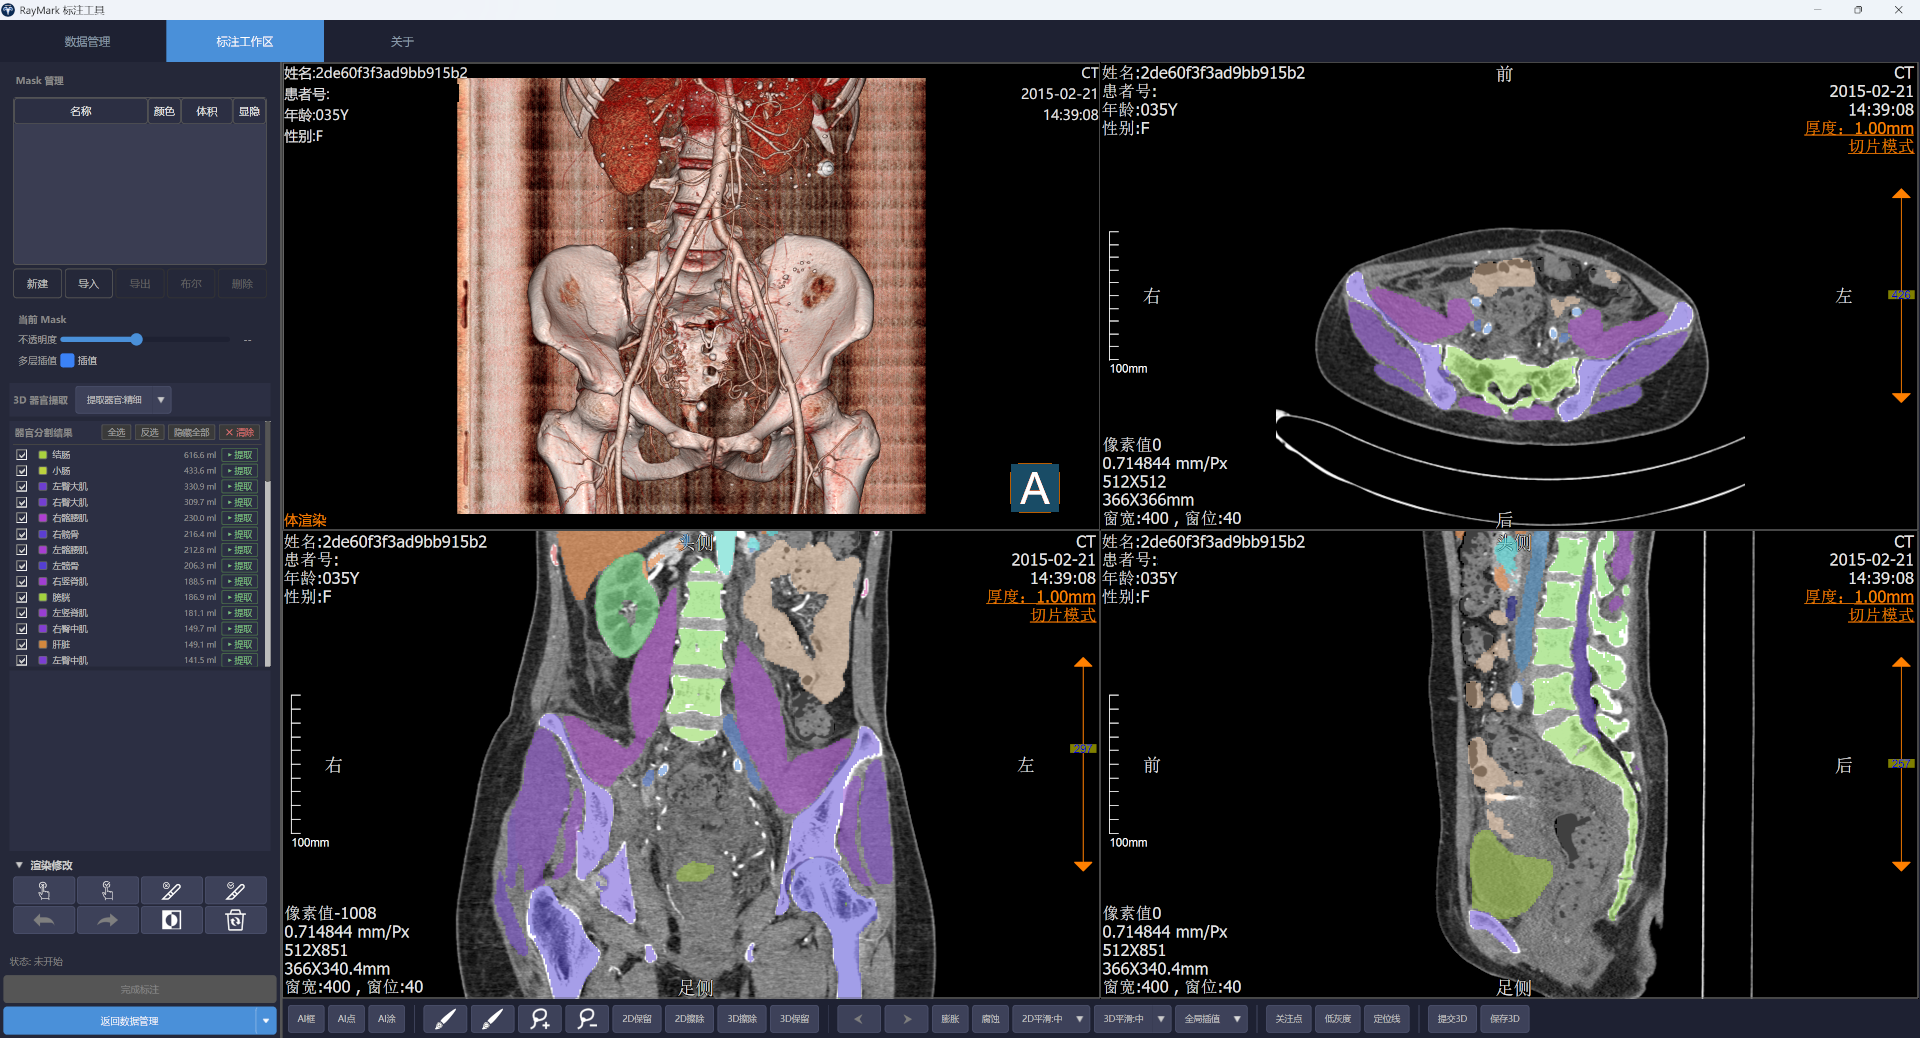

Windows macOS 2026年5月23日- 添加AI半自动分割功能(框选、点选、喷涂)

- 添加AI半自动分割多层传播功能

- 添加AI全自动器官分割功能

- 整体优化UI及交互逻辑

Windows macOS 2026年4月26日- 首次正式发布

- 支持DICOM数据批量导入与管理

- 支持医学影像标注与分割

- 支持标注数据导出与批量处理

- 支持DICOM数据匿名化处理